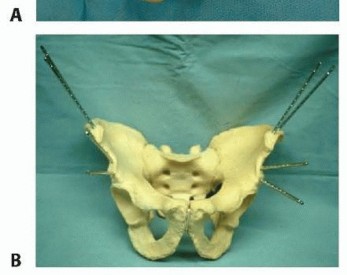

### FIG 5 • The anterior hemipelvis offers two sites for pin insertion: the iliac crest (superiorly) and the supraacetabular region (more inferiorly). A. Profile view. B. Frontal view. Pin placement within the iliac crest is more expeditiously performed and lacks significant regional anatomic hazards. On occasion, this area may be compromised by soft tissue concerns or proximity to fracture planes. In such cases, pin placement within the supra-acetabular region is an option. Pins and frames in this lower position may offer improved access to the abdomen and, unlike pins placed within the iliac crest, are less irritating to anterolateral abdominal soft tissues. 19 In an obese patient, these pins (supra-acetabular) may be better tolerated and less prone to loosening and infection. The dense bone of the supra-acetabular region offers stability of fixation as good as or better than the iliac crest. Some authors investigating the biomechanical performance of these pins (supra-acetabular) demonstrated superior purchase within bone and diminished displacement of posterior portions of the pelvic ring. 12 Because supra-acetabular pin insertion is more time consuming and instrumentation and fluoroscopy dependent, its role as a resuscitative measure is limited. The pelvic antishock clamp (C-clamp) is a posteriorly (or trochanteric) applied device that may offer greater stability to vertically unstable fractures than anteriorly applied frames ( FIG 6).1, 11 It is designed for the emergent treatment of unstable pelvic ring injuries. The device is indicated in both rotationally and vertically unstable pelvic ring injuries. It is contraindicated in lateral compression injuries and fractures involving comminution of the iliac wing or sacrum. If the device is used in lateral compression-type injuries, it may accentuate the deformity. Use of the pelvic 314 antishock clamp with iliac wing fractures may lead to the pins traversing the fracture sites, subsequently causing internal injury.

TECH FIG 5 • A,B. Pin clamps: straight and multiplanar. Applied pin clamps should remain three fingerbreadths above the skin surface. This is less threatening to subjacent soft tissues and permits adequate pin tract care. The frame is fabricated with inclusion of universal ball joints and reduction is performed. AP compression injuries are reduced with midline-directed compression and lateral compression injuries with distraction. Adjunctive lower extremity skeletal traction may be considered for vertically displaced patterns. Bar-to-bar connectors are next secured and operative incisions are closed and dressed. 4. ## Pelvic Antishock Clamp: C-Clamp The surgeon can choose between two coronally oriented pin placement positions (anterior or posterior) ( TECH FIG 6A).20 Anterior pins are placed in the dense column of bone of the gluteal ridge. Anterior pin placement will allow for compression of the anterior and, to some degree, the posterior pelvic ring. Posterior pin placement allows for compression of the posterior pelvic ring.

Landmarks for anterior pin placement include the anterior superior iliac spine, the tip of the greater trochanter, and the axis of the femur. The surgeon should ensure that the patient's legs are not externally rotated, as this will place pins too far posterior. The surgeon finds the gluteal ridge, which is three fingerbreadths posterior to the anterior superior iliac spine on the iliac wing. 320

C-E. Application landmarks and anterior pin site landmarks. F. Pelvic antishock clamp application landmarks and posterior pin site landmarks. (A: Modified from Buckle R, Browner B, Morandi M. Emergency reduction for pelvic ring disruptions and control of associated hemorrhage using the pelvic stabilizer. Tech Orthop 1995;9:258-266.) Next, the surgeon locates the tip of the greater trochanter and the axis of the femur with legs in neutral rotation. The center of the line connecting the gluteal ridge and the greater trochanter corresponds to the pin site. This point should be about 5 to 6 cm from the top of the iliac wing ( TECH FIG 6B-E). Landmarks for posterior pin placement include the anterior superior iliac spine, posterior superior iliac spine, and dorsal axis of the femur. A line is drawn between the anterior and posterior superior iliac spines. The intersection of this line and the dorsal axis of the femur corresponds to the pin site. The pin site should be about 4 to 5 cm anterior to the posterior iliac spine ( TECH FIG 6F). The surgeon must avoid the greater sciatic notch and the soft bone of the iliac fossa. The pin site is infiltrated with local anesthetic and an incision is made. Blunt dissection is carried down to bone. The pins are adjusted to be in a single axis. This orientation allows rotation of the C-clamp, permitting abdominal access. Reduction of any vertical displacement is now completed with traction. Alternatively, the C-clamp may be directly applied to the trochanteric region of the femur. 1 The anatomic hazards of the previous method of application are thus avoided. In this manner, it serves a role similar to circumferential sheeting.